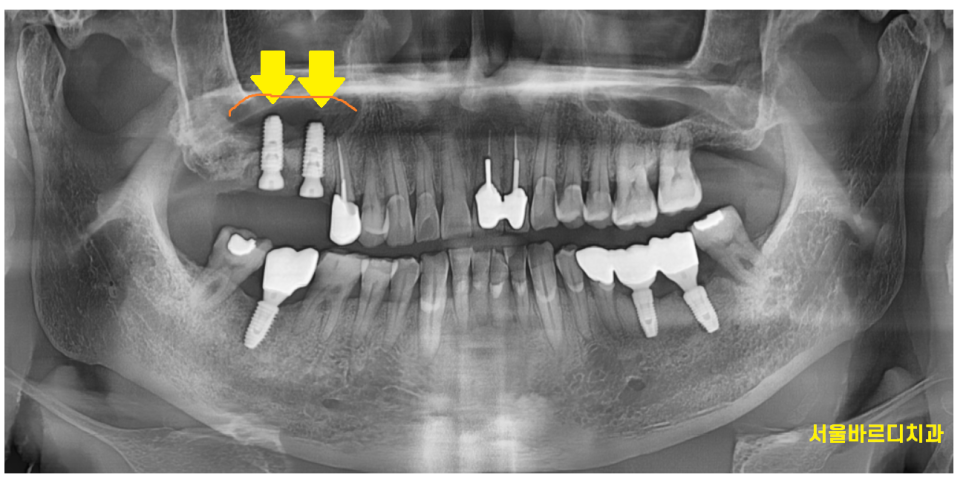

23.07.04

역시나 잇몸뼈가 머리까지 차 있어야하는데

많이 내려가 있는것이 보입니다.

전체 28개의 치아중에서

유독 안좋아보이는 오른쪽 윗니 치아

추가적으로 검사를 해보았는데요.

큰 어금니 2개 상태가 영 ㅠㅠ 별로네요.

잇몸뼈가 많이 내려가다보니

어금니 시림 현상이 발생